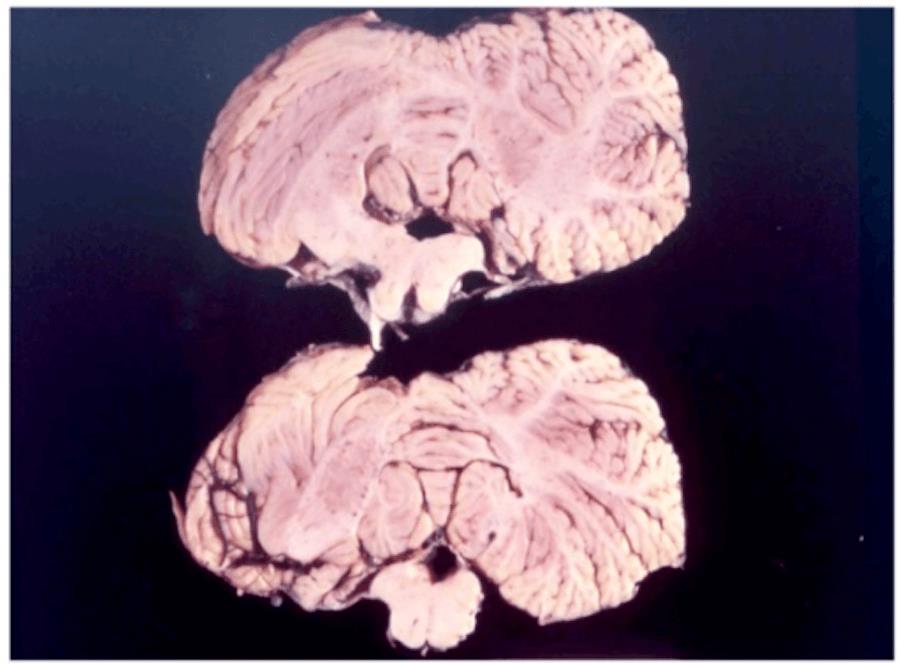

Khi ông Gajdusek và Gibbs khám nghiệm tử thi con vật, họ phát hiện ra rằng não của nó, đặc biệt là tiểu não - nơi điều khiển sự phối hợp của các cơ, có hàng triệu lỗ cực nhỏ, khiến não trông giống một miếng bọt biển hoặc pho mát Thụy Sĩ dưới kính hiển vi. Thí nghiệm này không chỉ xác nhận rằng Kuru lây lan qua mô bị nhiễm bệnh và bệnh tấn công trực tiếp vào não, mà còn là một trường hợp cực kỳ hiếm gặp về bệnh lây truyền từ loài này sang loài khác trong môi trường phòng thí nghiệm và là trường hợp đầu tiên được biết đến về rối loạn thoái hóa thần kinh truyền nhiễm.

Các lỗ giống như miếng bọt biển mà prion gây ra trong mô não của nạn nhân là thứ khiến bệnh Kuru, CYD, scrapie và các bệnh tương tự có tên gọi chung là bệnh não xốp có thể lây truyền. Cái tên đó nghe có vẻ quen thuộc vì prion cũng là nguyên nhân gây ra bệnh não xốp ở bò (BSE) hay còn được gọi là bệnh bò điên. Giống như Kuru, BSE cũng lây lan qua ăn thịt đồng loại, mặc dù dưới hình thức khác.